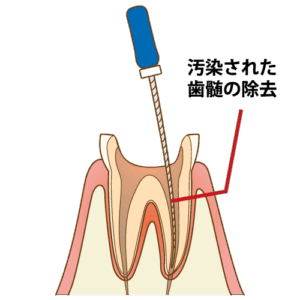

⏫②歯の中の治療をしていくので、治療の入り口を作らなければいけません。

神経の感染部分まで機械を使って削っていきます。

※ここから5〜7日に1回のペースで通っていただきます。